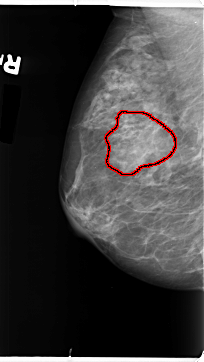

ics_version 1.0 filename B-3101-1 DATE_OF_STUDY 7 11 1996 PATIENT_AGE 48 FILM FILM_TYPE REGULAR DENSITY 3 DATE_DIGITIZED 6 2 1998 DIGITIZER LUMISYS LASER SEQUENCE LEFT_CC LINES 4632 PIXELS_PER_LINE 2632 BITS_PER_PIXEL 12 RESOLUTION 50 NON_OVERLAY LEFT_MLO LINES 4744 PIXELS_PER_LINE 2792 BITS_PER_PIXEL 12 RESOLUTION 50 NON_OVERLAY RIGHT_CC LINES 4720 PIXELS_PER_LINE 2472 BITS_PER_PIXEL 12 RESOLUTION 50 OVERLAY RIGHT_MLO LINES 4696 PIXELS_PER_LINE 2640 BITS_PER_PIXEL 12 RESOLUTION 50 OVERLAY |

FILE: B_3101_1.RIGHT_MLO.OVERLAY TOTAL_ABNORMALITIES 1 ABNORMALITY 1 LESION_TYPE MASS SHAPE IRREGULAR-FOCAL_ASYMMETRIC_DENSITY MARGINS ILL_DEFINED ASSESSMENT 3 SUBTLETY 2 PATHOLOGY BENIGN TOTAL_OUTLINES 1 BOUNDARY |